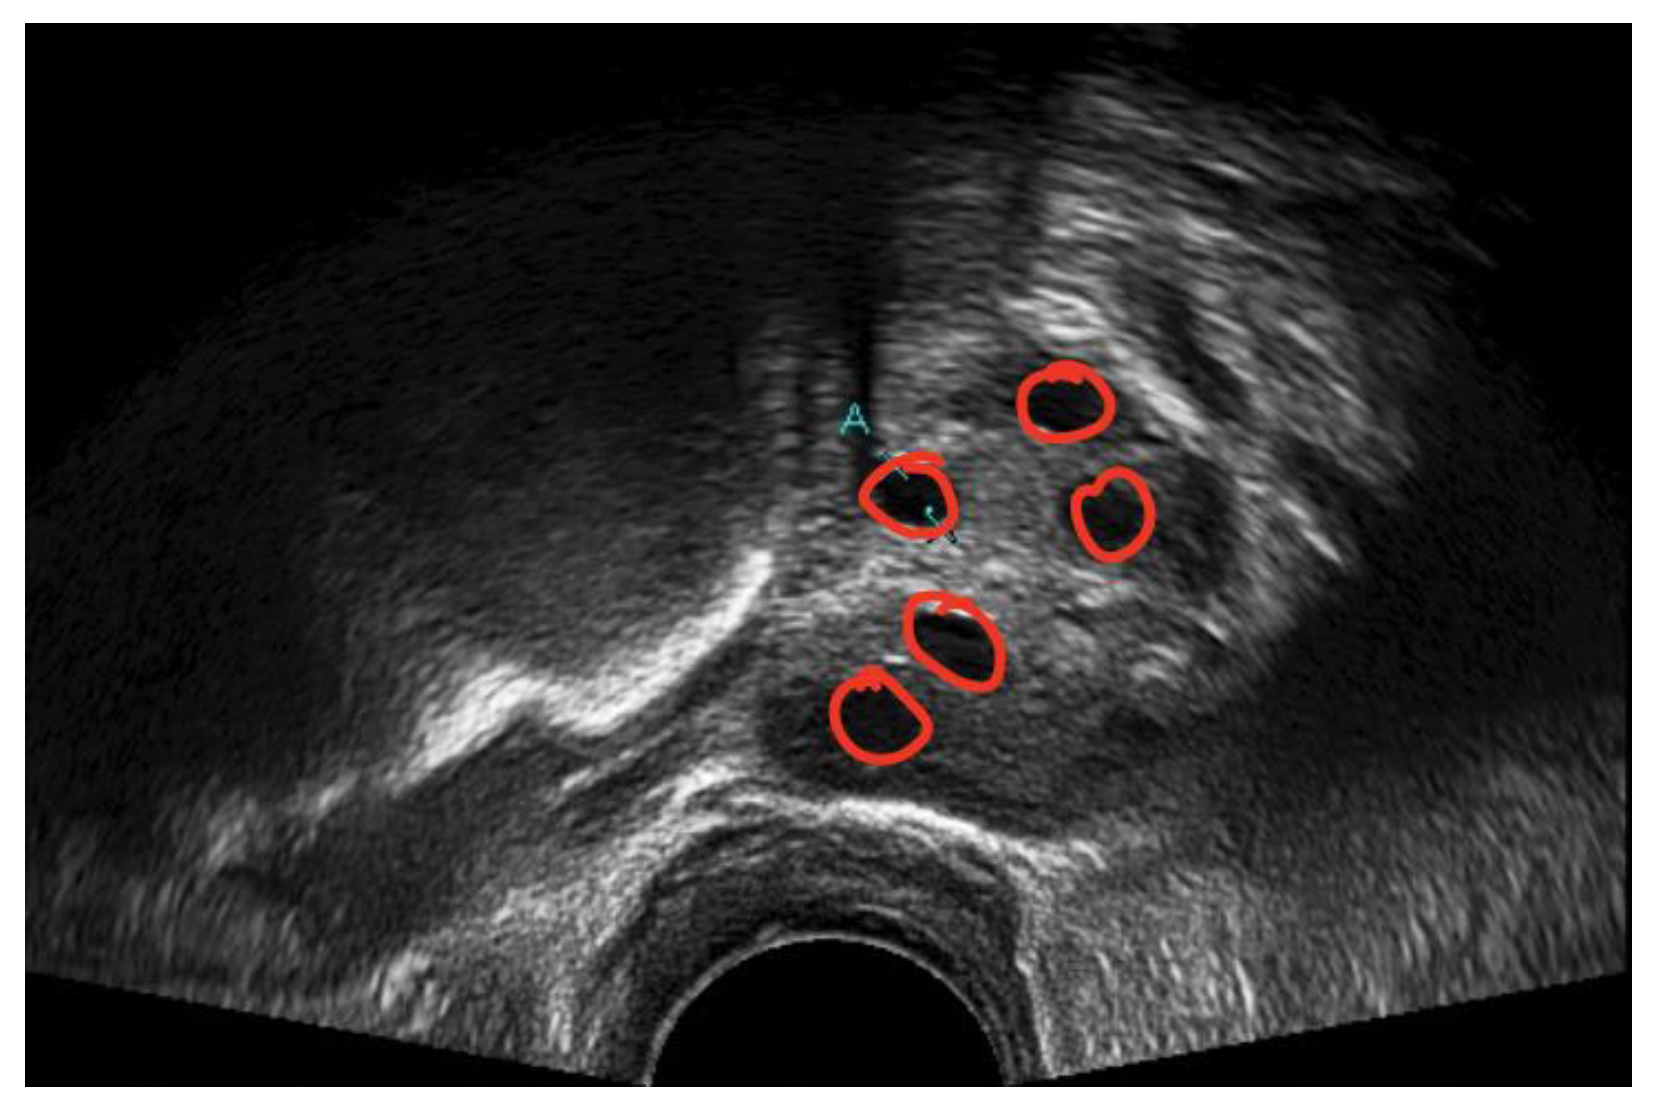

A medical expert was asked to mark the follicle boundary in the ultrasound image to be the ground truth, because this study will be implemented on local ultrasound images. Figure 7 shows the original ultrasound images that were collected by medical experts during patient monitoring, and Figure 8 shows the ultrasound images marked with red circles by medical experts to highlight the existing follicles.

Figure 8.

Image of identified follicles marked by medical expert.